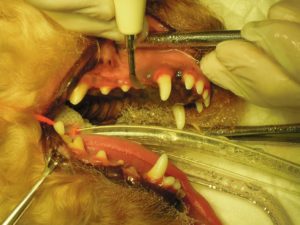

4.プロービング検査で歯周ポケットの深さを測定して